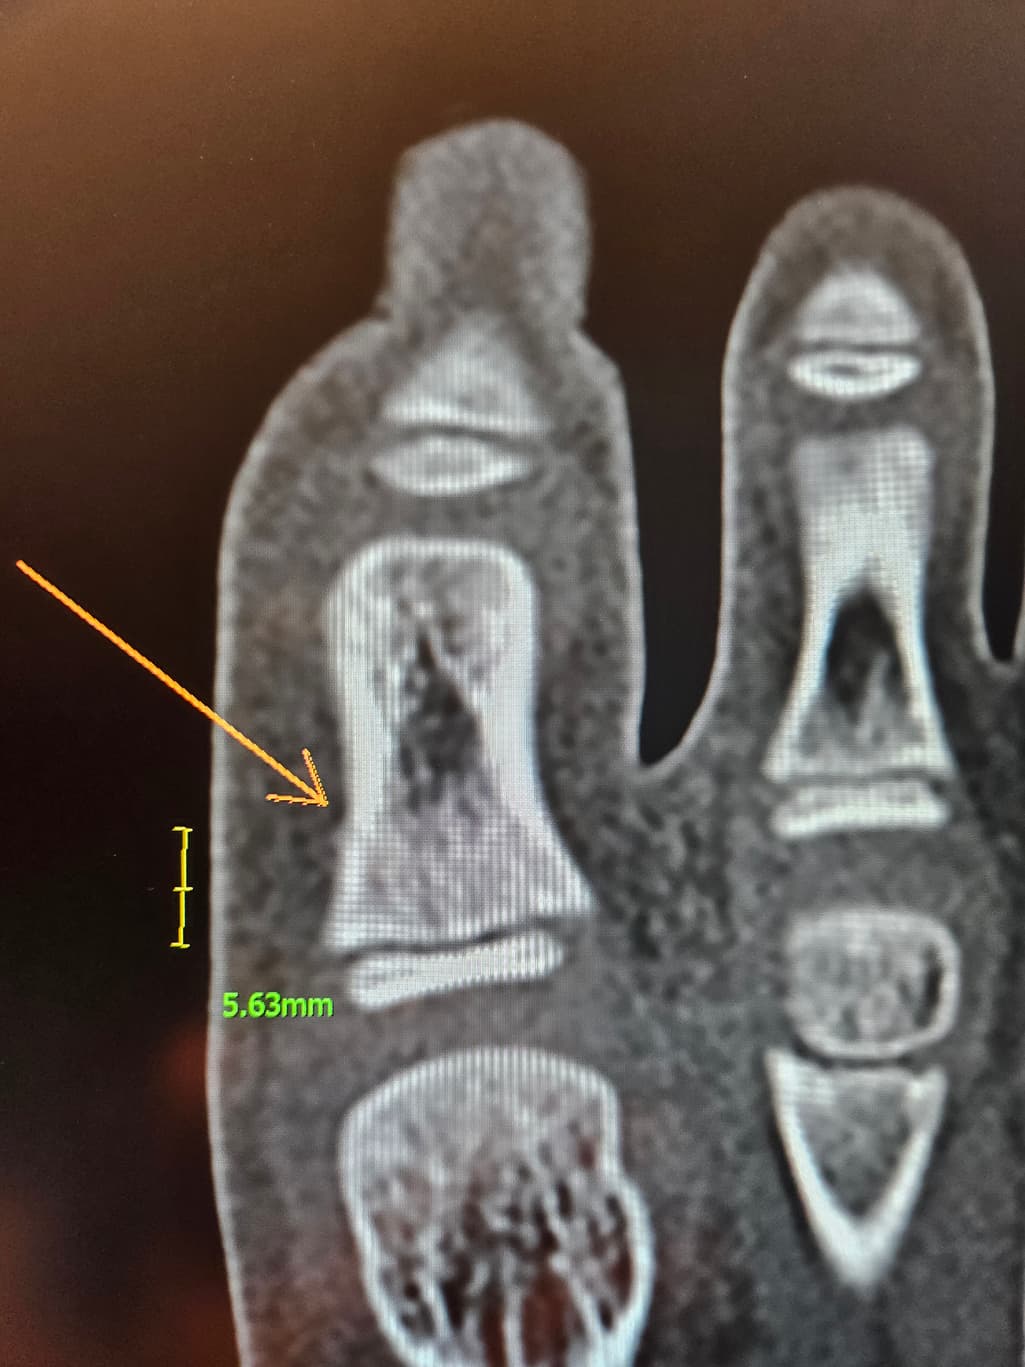

두번째 세번째는 ct입니다

수술하자하는데 제가 일주일만 경과보고프다해서 일단 통깁스만했는데ㅠ

핀 수술이 필요할까요?ㅠ